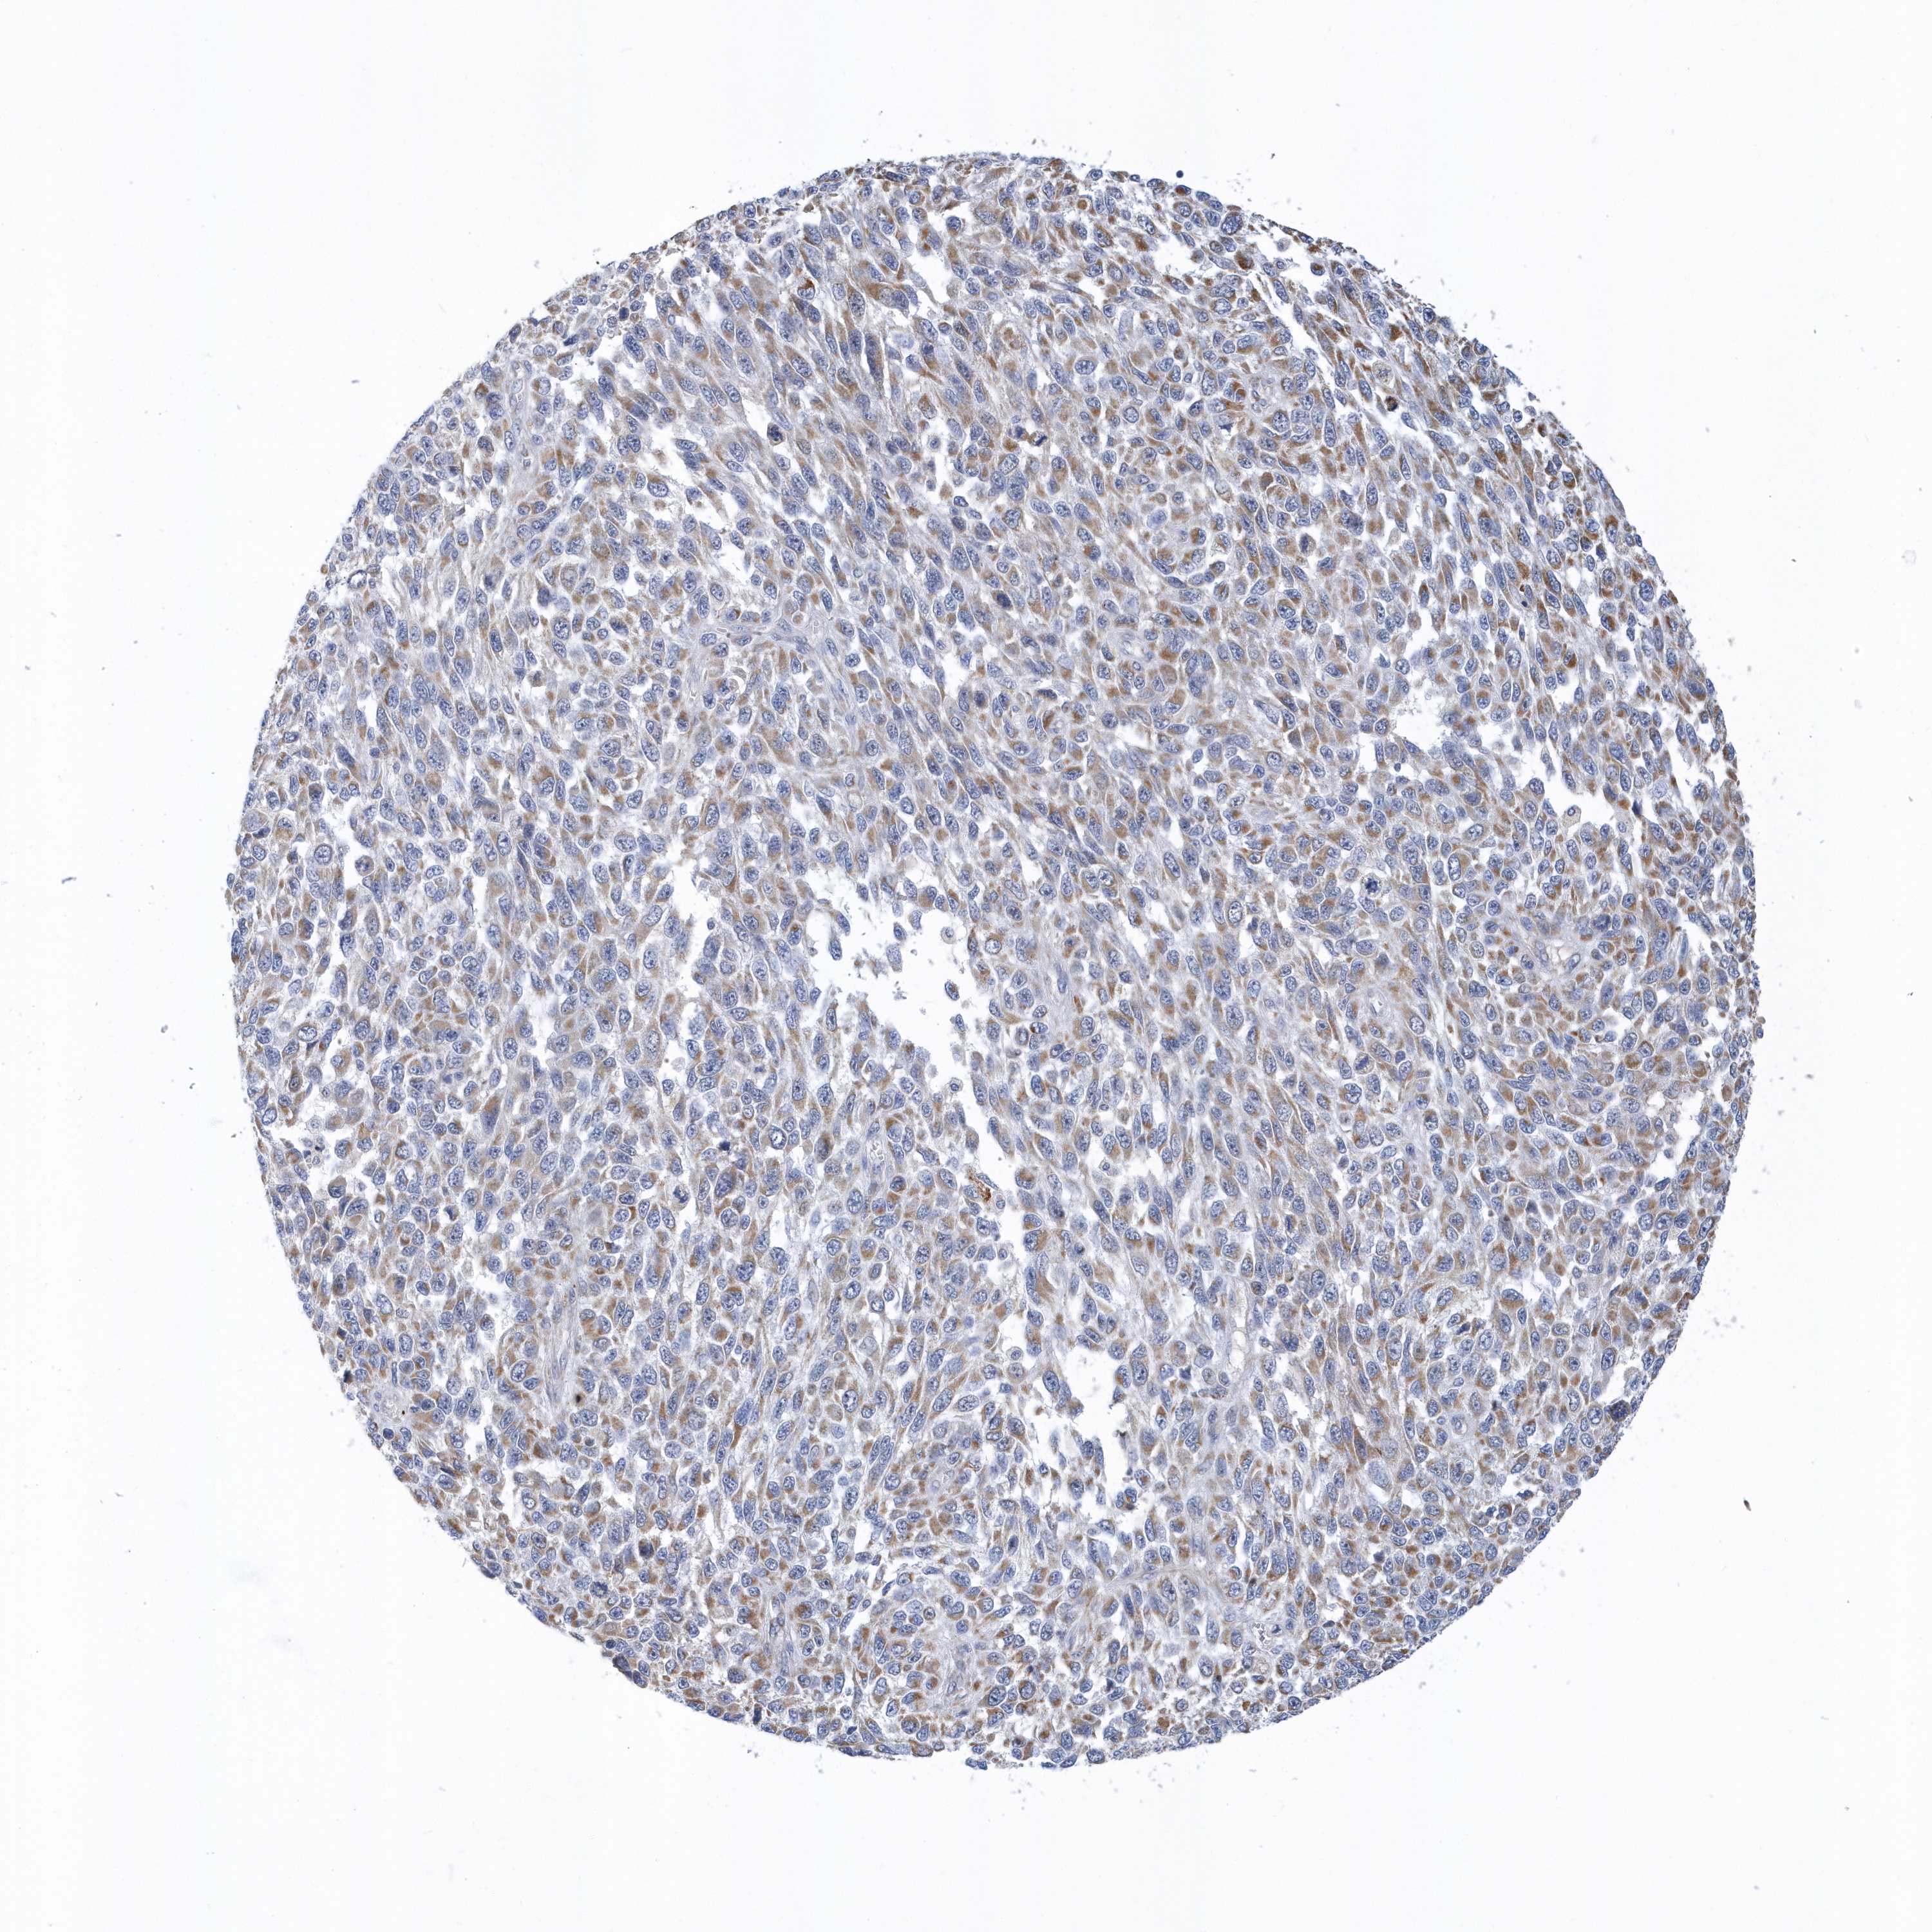

MELANOMA - Protein expressioni

A mouse-over function shows sample information and annotation data. Click on an image to view it in a full screen mode. Samples can be filtered based on level of antibody staining by selecting one or several of the following categories: high, medium, low and not detected. The assay and annotation is described here.

Note that samples used for immunohistochemistry by the Human Protein Atlas do not correspond to samples in the TCGA dataset.

Antibody stainingi

Antibody staining in the annotated cell types in the current human tissue is reported as not detected, low, medium, or high, based on conventional immunohistochemistry profiling in selected tissues. This score is based on the combination of the staining intensity and fraction of stained cells.

Each image is clickable and will lead to virtual microscopy that enables deeper exploration of all samples and also displays staining intensity scores, fraction scores and subcellular localization as well as patient and tissue information for each sample.

Antibody HPA036823

Antibody HPA036824

Antibody HPA061412

Staining

High

Medium

Low

Not detected

Intensity

Strong

Moderate

Weak

Negative

Quantity

>75%

75%-25%

<25%

None

Location

Nuclear

Cytoplasmic/membranous

Cytoplasmic/membranous,nuclear

Malignant melanoma, NOS

Malignant melanoma, Metastatic site